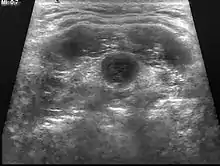

| Ultrasound | Image capture of the degree of mass and its surrounding tissues. |